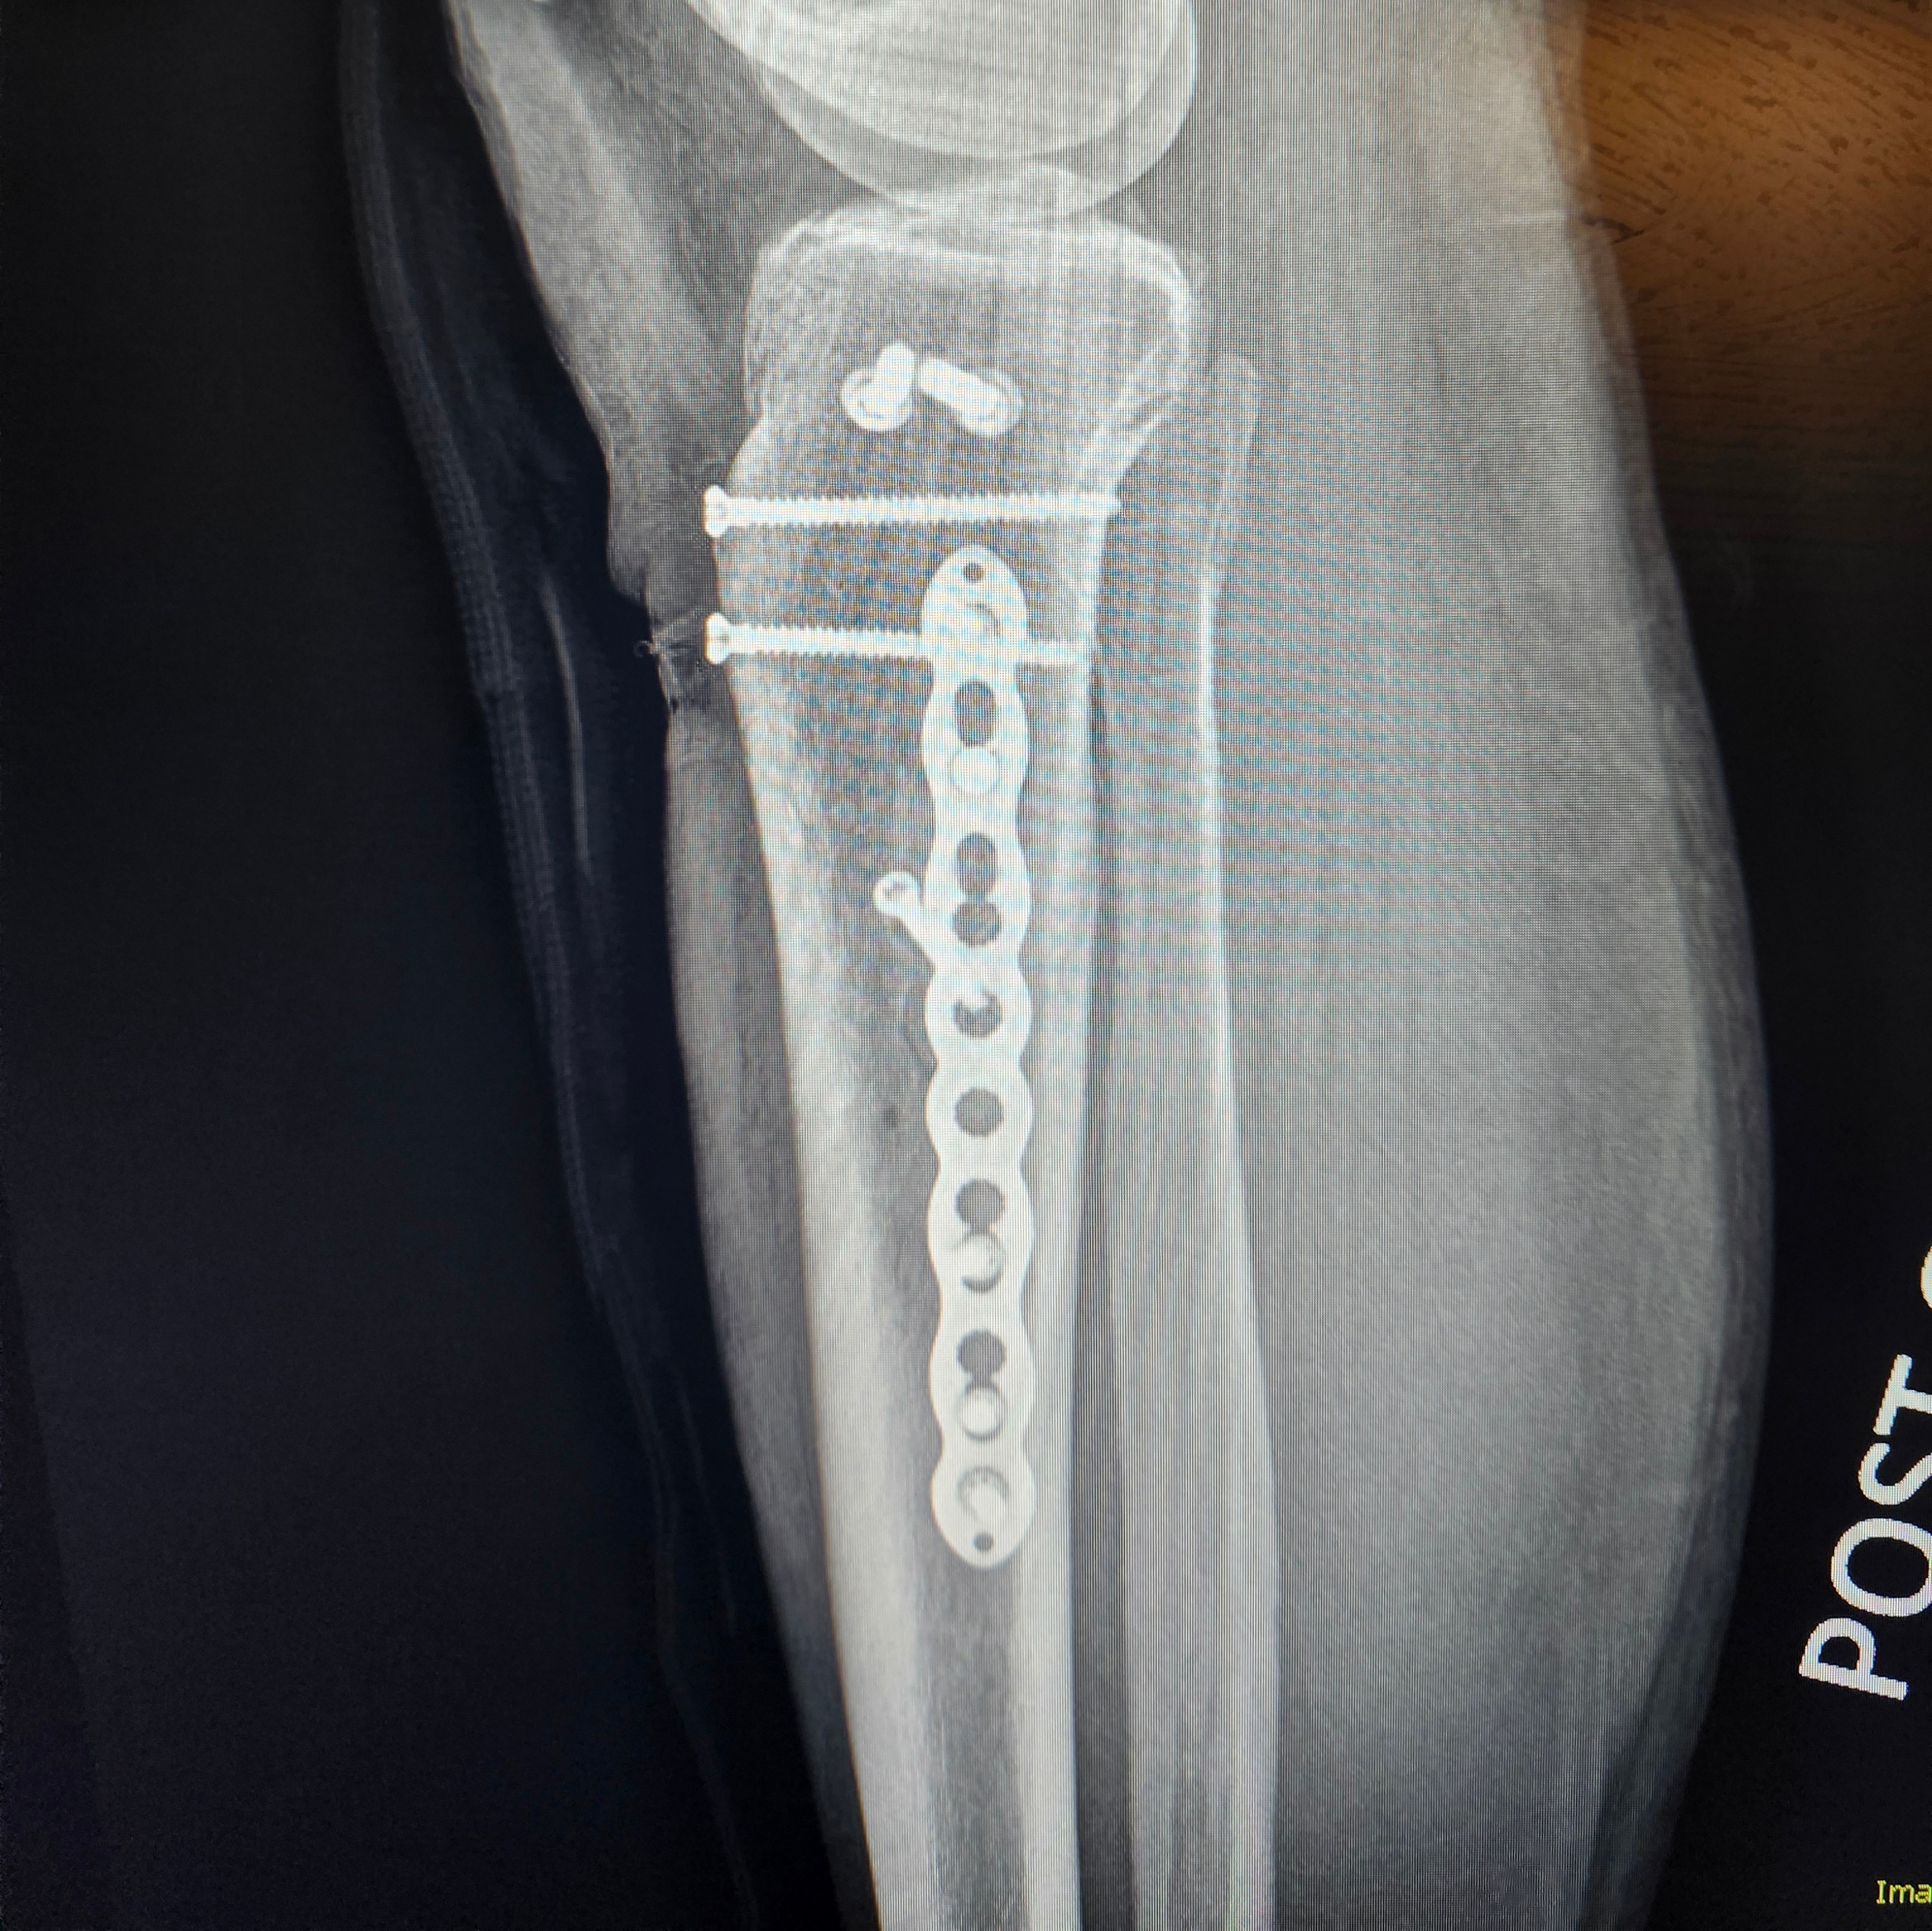

One day, Adriane was doing what she loved, teaching Kundalini yoga, helping others heal, and living her life with purpose and compassion. On February 14th, she had a devastating accident and was rushed into emergency surgery. Nothing prepares you for that phone call. Nothing prepares you to see someone you love in that much pain. She was in the hospital for 5 days before she was stable enough to come home. The surgery was successful, leaving her with a metal plate and several screws in her tibia. She now faces a long, painful recovery. She cannot stand, she cannot teach, and she cannot work. The career she built with so much love and dedication is suddenly out of reach while her body tries to heal.